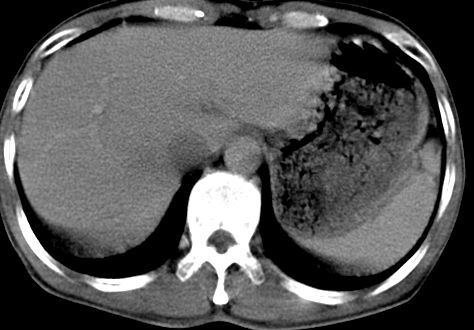

病人资料:男,50岁,上腹部隐痛,消瘦乏力,有乙肝病史二十余年,b超提示肝内内占位。

由于是基层医院,机器速度跟不上,增强效果差,请各位老师也看看!

肝右叶后下内侧段占位:肝癌可能性大

肝内占位,考虑肝局灶性结节增生,不除外肝癌.胰尾好象有占位?

肝右叶后段低密度灶,增强受机器限制,特点不明显,无等密度充填及周围强化,结合病人乙肝史20年,首先考虑肝癌。

肝右后叶占位,增强时期没抓好,特点不明显,结合病史首先考虑原发性肝癌

考虑肝右叶后下内侧段占位:肝癌可能性大。增强效果很不理想。